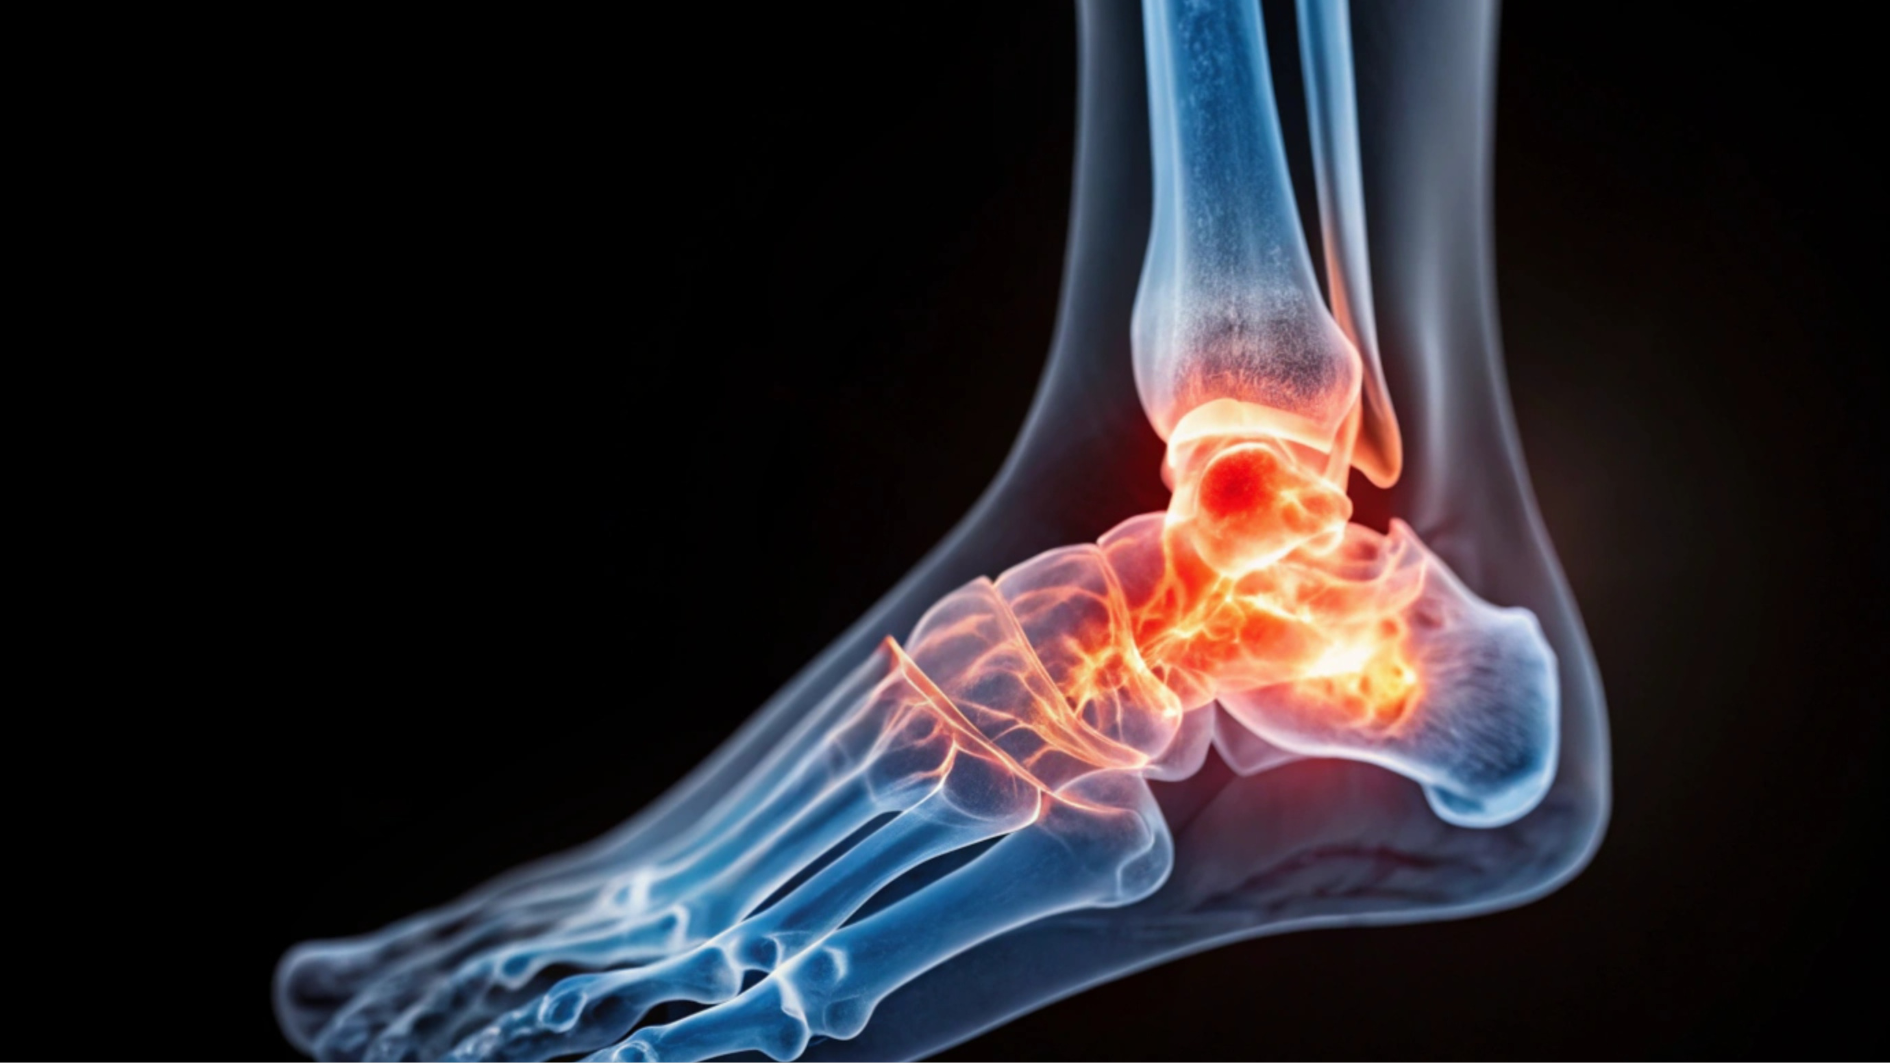

Đối với những người có bệnh nền như tiểu đường hoặc bệnh thần kinh ngoại vi, khi cảm thấy đau ở chân, mắt cá hoặc bàn chân, việc thăm khám sớm là rất quan trọng. Bác sĩ sẽ đưa ra phác đồ điều trị phù hợp nhằm phòng ngừa các biến chứng nguy hiểm có thể xảy ra.

Kê cao vùng bị thương

Đặc biệt đối với tổn thương ở chân, mắt cá hoặc bàn chân, nên kê cao vị trí bị nứt xương khi nằm nghỉ. Điều này giúp giảm sưng, cải thiện lưu thông máu và hỗ trợ quá trình hồi phục xương.